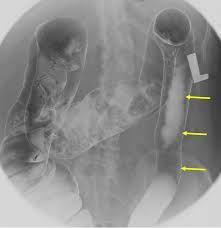

strictures (String sign)

lead pipe sign, UC

string sign, CD